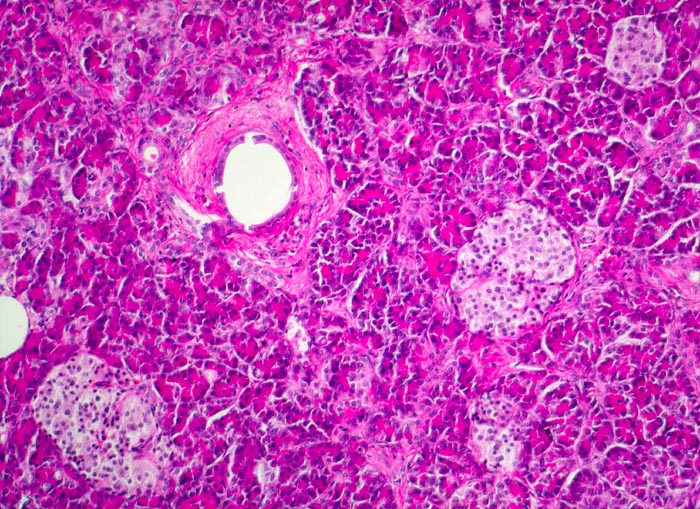

PathoPic – image database / PathoPic ID 4351 - Normales endokrines Pankreas: Langerhans Inseln

Normales endokrines Pankreas: Langerhans Inseln

Rundliche helle Zellinseln im Pankreasparenchym. Die Inselzellen sind kleiner und blasser als die Azinuszellen. Sie sind zu kleinen Gruppen (Inseln) innerhalb der exokrinen Azini angeordnet. Im Bildzentrum ein kleiner Ausführungsgang.

Die Langerhans Inseln sind am zellreichsten im Schwanzbereich und können sehr unterschiedlich gross sein. Zelltypen: 70% B-Zellen bilden Insulin und Amilin, 20% A-Zellen bilden Glukagon, 5-10% D-Zellen bilden Somatostatin, 1-2% PP-Zellen bilden pankreatisches Polypeptid. Die übrigen Zellen bilden VIP oder gemischte Sekrete (Enterochromaffine Zellen).